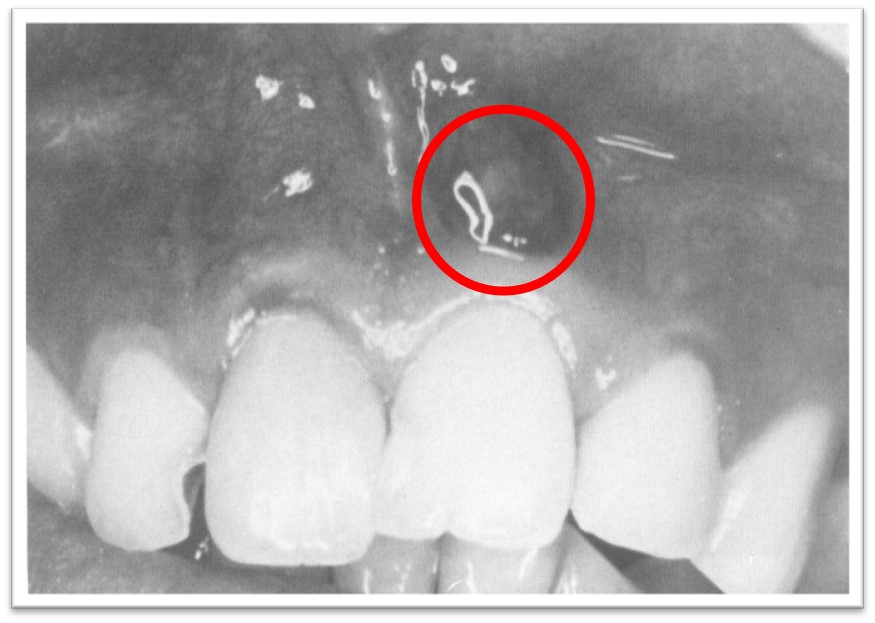

3、黏膜下或皮下脓肿(图9.1-1),有波动感或溢脓。

图9.1-1 黏膜下脓肿